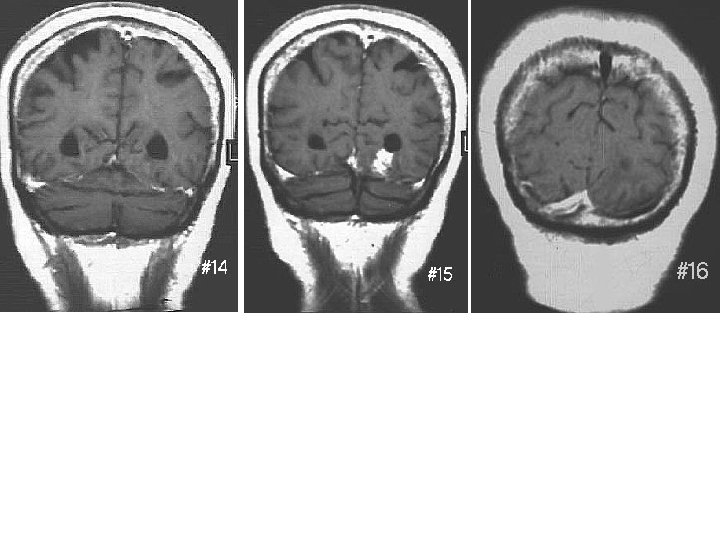

Not These Not these This one Not these

14 points 1. Frontal (anterior) horn of Lateral ventricle 2. Body (central part) of

14 points 1. Frontal (anterior) horn of Lateral ventricle 2. Body (central part) of lateral ventricle 1 3. Trigone of lateral ventricle (not in Netter) 6 4. Occipital (posterior) horn of lateral ventricle 7 5. Temporal (inferior) horn of lateral ventricle 6. Interventricular foramen (of Monro) 7. Interthalamic adhesion 8. 3 rd ventricle 9. Cerebral aqueduct (of Sylvius)* 10. 4 th ventricle 11. Foramen of Luschka 12. Lateral recess 13. Median aperture (Foramen of Magendie) 14. Central canal of spinal cord See plate 102 -103 2 8 3 9 4 5 10 11 12 13 Ventricular System Drawing 14